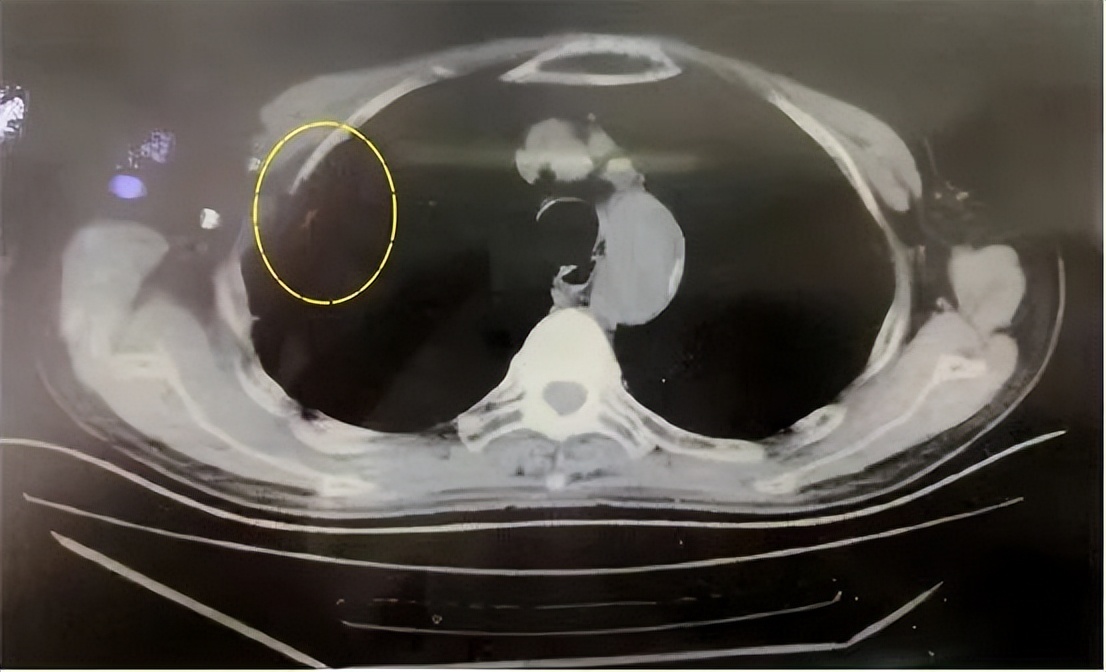

患者右上肺小肺癌,本身年龄大、身体情况差,拒绝手术治疗。

CT引导下射频针插入右上肺癌,高温消融灭活肿瘤。

半年后复查,肺癌灭活基本吸收消失。